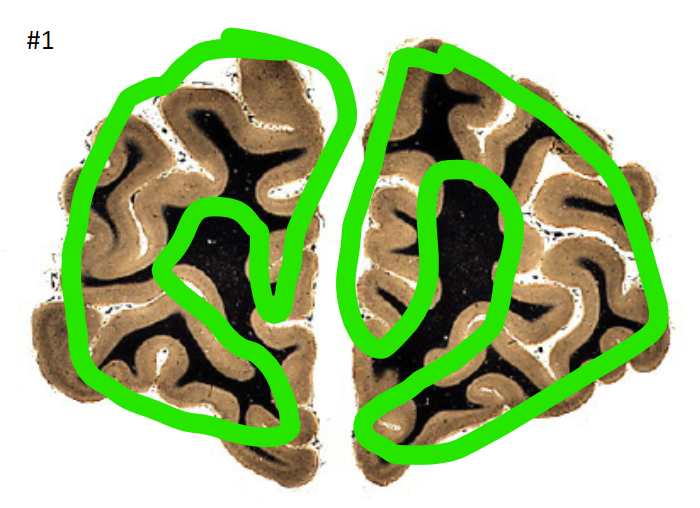

1

Q

what is the circled area (#1)?

A

the cortex

2

White matter